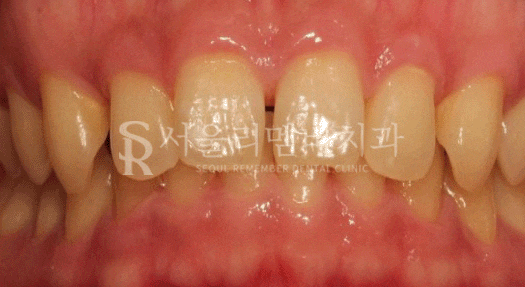

윗니가 아랫니를 너무 깊게 문다며 상도동치과 를 내원해 주셨는데요.

초진 사진을 보면 한눈에 봐도 아랫니가 거의 보이지 않을 정도로

수직 피개량이 크게 나타나고 있는 것을 볼 수 있었습니다.

과하게 물리던 앞니의 모습은 사라지고 정상 피개량으로 개선이 되었습니다.

또한 악궁 및 배열 상태도 전에 비해 더 긴밀하게 바뀐 것을 볼 수 있었는데요.

안모 사진이 없어 아쉽지만, 웃는 모습도 한결 편안하고 단정하게 나아지셨던 환자분!

이를 뽑지 않고 이렇게 나아질 수 있어서 너무 좋다는 말씀을 남겨주셨습니다ㅎㅎ